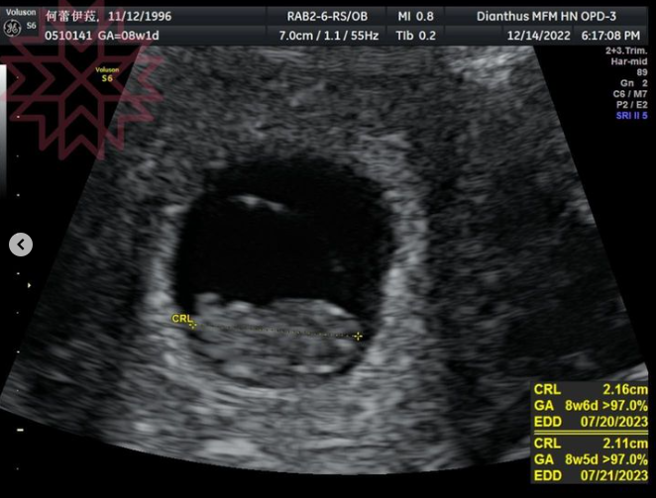

蕾菈晒超音波照。(图/IG@la.112814)

蕾菈晒超音波照。(图/[email protected]